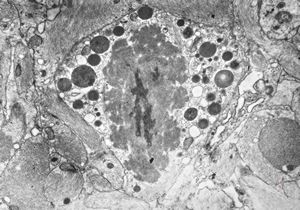

F,50y. | progressive multifocal leukoencephalopathy- viral particles in a glial cell

F,50y. | progressive multifocal leukoencephalopathy- viral particles in a glial cell

F,50y. | progressive multifocal leukoencephalopathy- viral particles in a glial cell